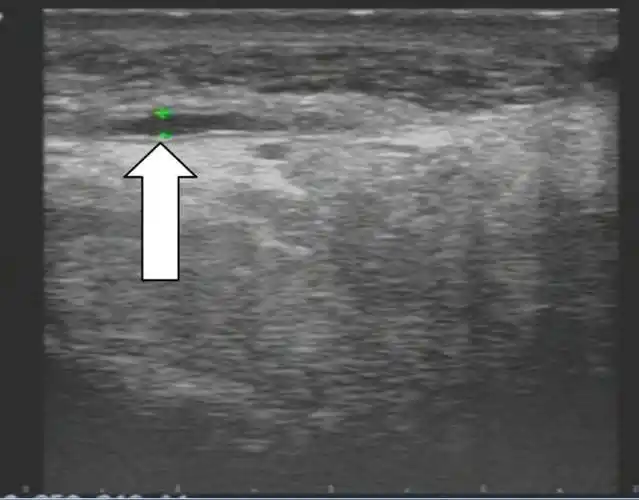

正常受试者与早泄患者的精囊腺超声图

正常精囊腺超声